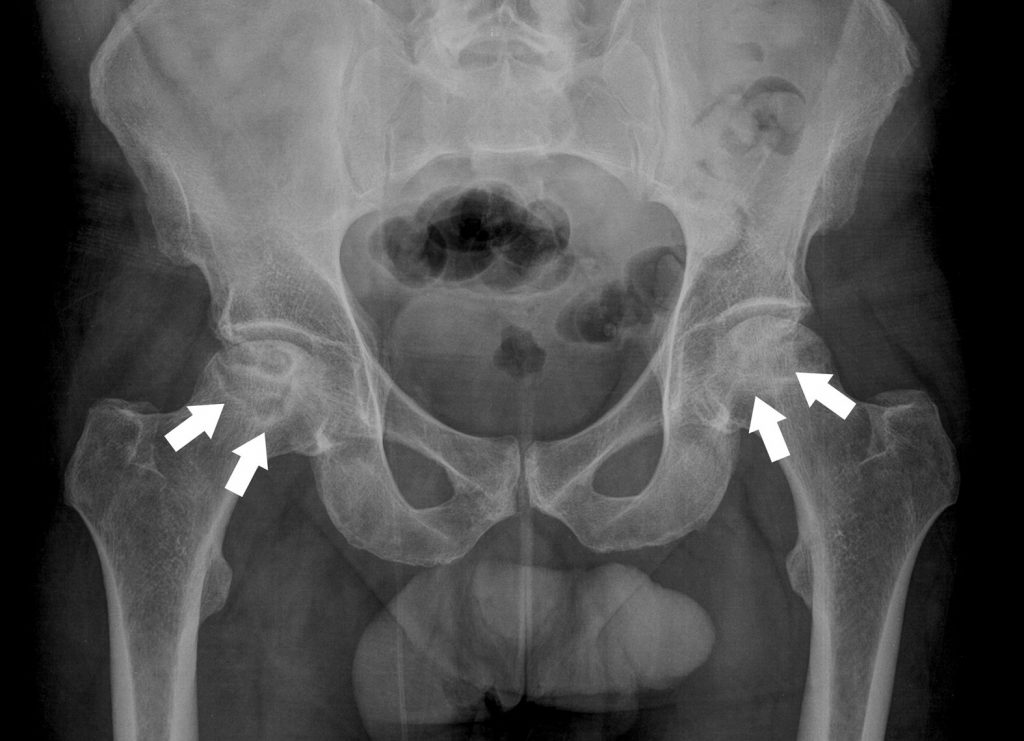

Fig. 85.4 Ostéonécrose bilatérale des têtes fémorales.

Radiographie du bassin de face montrant des liserés de sclérose (flèches) en périphérie des zones nécrosées avec une perte de sphéricité de la tête fémorale déjà visible à droite.

Source : CERF, CNEBMN, 2022.